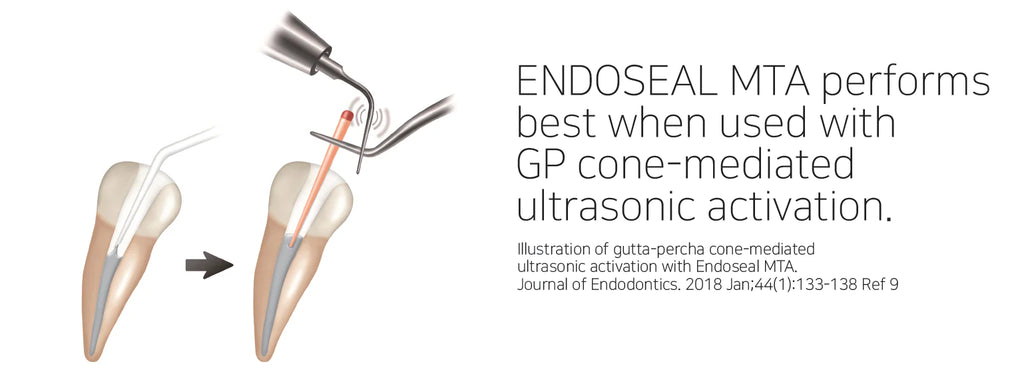

ENDOSEAL MTA is a paste-type root canal sealer based on pozzolan cement that has excellent physical and biological properties of MTA. It is premixed and pre-loaded in a syringe that allows direct application of the sealer into the root canal without requiring powder/liquid mixing, unlike other products. The product has outstanding flowability and maneuverability, which makes it possible to completely fill the root canal system including accessory and lateral canals. It is eugenol-free and will not impede adhesion inside the root canal.